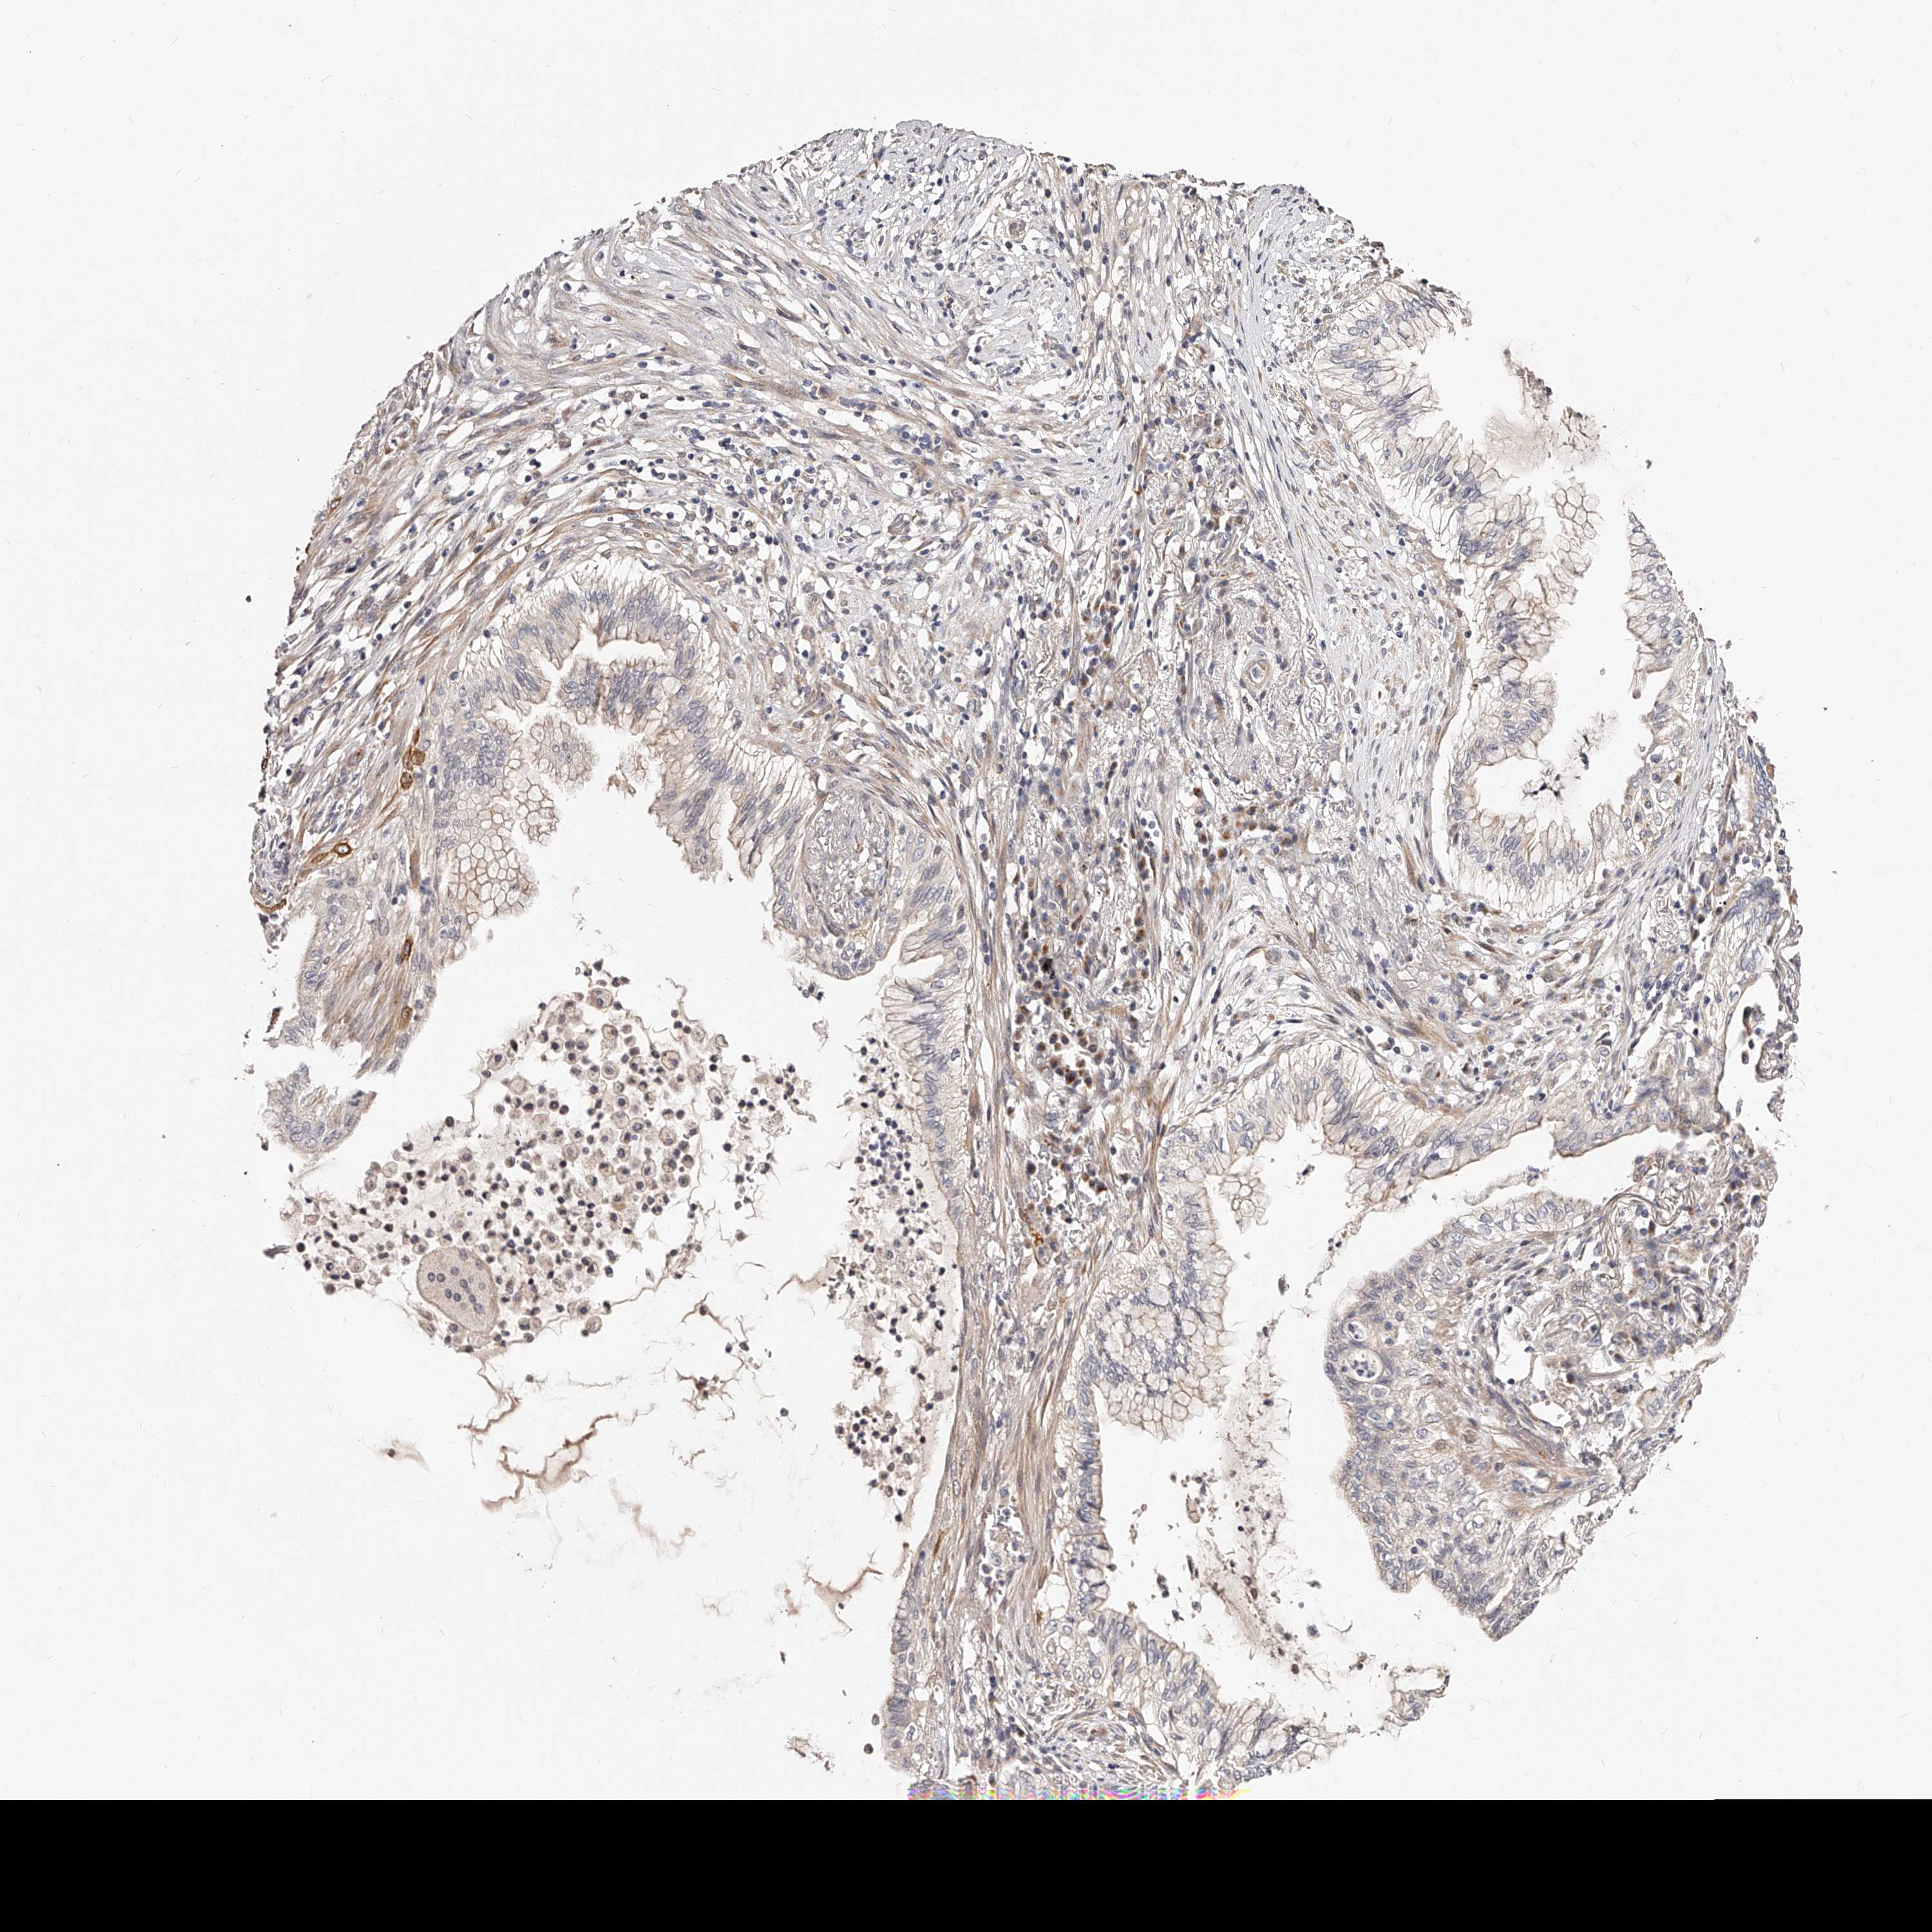

LUNG ADENOCARCINOMA (VALIDATION) - Interactive survival scatter ploti

The Survival Scatter plot shows the clinical status (i.e. dead or alive) for all individuals in the patient cohort, based on the same data that underlies the corresponding Kaplan-Meier plots. Patients that are alive at last time for follow-up are shown in blue and patients who have died during the study are shown in red.

The x-axis shows the expression levels (FPKM) of the investigated gene in the tumor tissue at the time of diagnosis. The y-axis shows the follow-up time after diagnosis (years). Both axes are complimented with kernel density curves demonstrating the data density over the axes. The top density plot shows the expression levels (FPKM) distribution among dead (red) and alive patients (blue). The right density plot shows the data density of the survived years of dead patients with high and low expression levels respectively, stratified using the cutoff indicated by the vertical dashed line through the Survival Scatter plot. This cutoff is automatically defined based on the FPKM cutoff that minimizes the p-score. The cutoff can be changed by dragging the vertical line or by entering a cutoff value in the square labeled "Current cut-off".

Under the Survival Scatter plot the p-score landscape (black curve; left axis) is shown together with dead median separation (red curve; right axis). Dead median separation is the difference in median mRNA expression between patients who have died with high and low expression, respectively. It is calculated as follows: median FPKM expression of dead patients with high expression - median FPKM expression of dead patients with low expression. This is intended to aid the user in visually exploring custom cutoffs and the associated p-scores and dead median separation.

Individual patient data is displayed and can be filtered by clicking on one or more of the category buttons on the top of the page. Categories describing expression level and patient information include: high, low, alive, dead, female, male and tumor stages. The scale of the x-axis can be toggled between linear and log-scale by clicking on the "x log" button. Mouse-over function shows TCGA ID, patient information and mRNA expression (FPKM) for each patient.

& Survival analysisi

Kaplan-Meier plots summarize results from analysis of correlation between mRNA expression level and patient survival. Patients were divided based on level of expression into one of the two groups "low" (under cut off) or "high" (over cut off). X-axis shows time for survival (years) and y-axis shows the probability of survival, where 1.0 corresponds to 100 percent.

ZNF502 is not prognostic in Lung Adenocarcinoma (validation)

Best expression cut offi

Based on the FPKM value of each gene, patients were classified into two groups and association between prognosis (survival) and gene expression (FPKM) was examined. The best expression cut-off refers the FPKM value that yields maximal difference with regard to survival between the two groups at the lowest log-rank P-value. Best expression cut-off was selected based on survival analysis .

When clicking on this number, the vertical dashed line indicating cut-off, the interactive survival plot, and the Kaplan-Meier curve will be adjusted to show results based on the best expression cut-off.

: 1.48

P scorei

Log-rank P value for Kaplan-Meier plot showing results from analysis of correlation between mRNA expression level and patient survival.

N/A

TCGA RNA samplesi

RNA-seq data is reported as average FPKM (number Fragments Per Kilobase of exon per Million reads), generated by the The Cancer Genome Atlas (TCGA) .

Normal distribution across the dataset is visualized with box plots, shown as median and 25th and 75th percentiles. Points are displayed as outliers if they are above or below 1.5 times the interquartile range. FPKM values of the individual samples are presented next to the box plot.

Average pTPM 1.9

Number of samples 105